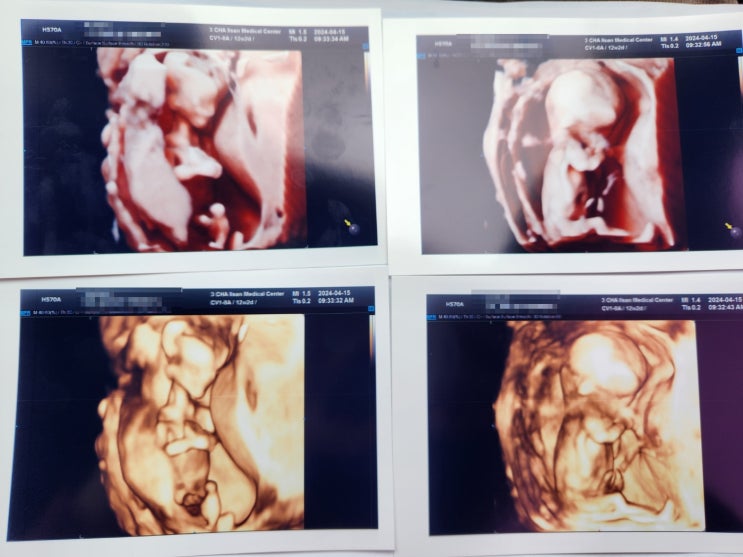

[임신일기] 14~16주 기록 - 난소 혹/성별 확인/반전 없는 성별/입덧완화/베이비페어

# 14~16 주차 기록 난소 혹/성별 확인/반전 없는 성별/ 입덧완화/베이비페어 2024년 4월 29일, 월요일 14주...